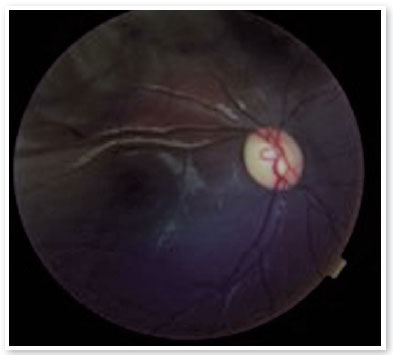

Ao exame oftalmológico, refração estática de +1,50D esférica em ambos os olhos (AO) com acuidade visual de 20/20 em olho direito (OD), 20/100 parcial em olho esquerdo (OE) e alteração no teste de cores de Ishihara. Motilidade ocular extrínseca sem alterações. À biomicroscopia, pupilas isocóricas e fotorreativas com nodulações hamartomatosas irianas em AO, mais concentradas inferiormente, sugestivas de nódulos de Lisch (Figura 1). Gonioscopia demonstrando ângulo aberto até corpo ciliar em AO. Fundoscopia demonstrou palidez de papila óptica bilateral mais acentuada em OE, relação escavação/disco de 0,4 OD e 0,8 OE (Figuras 2 e 3). Pressão intraocular de 12mmHg em ambos os olhos. À inspeção geral, presença de inúmeras manchas hipercrômicas do tipo “café-com-leite” distribuídas em tronco (Figura 4) e dorso (Figura 5).